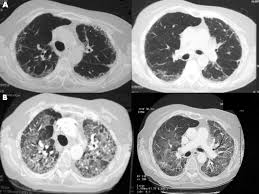

Bronchiectasis is an uncommon disease, most often secondary to an infectious process, that results in the abnormal and permanent distortion of one or more of the conducting bronchi or airways. First described by Laennec in 1819, later detailed by Sir William Osler in the late 1800s, and further defined by Reid in the 1950s, bronchiectasis has undergone significant changes in regard to its prevalence, etiology, presentation, and treatment.Bronchiectasis can be categorized as a chronic obstructive pulmonary disease manifested by airways that are inflamed and easily collapsible, resulting in air flow obstruction with shortness of breath, impaired clearance of secretions